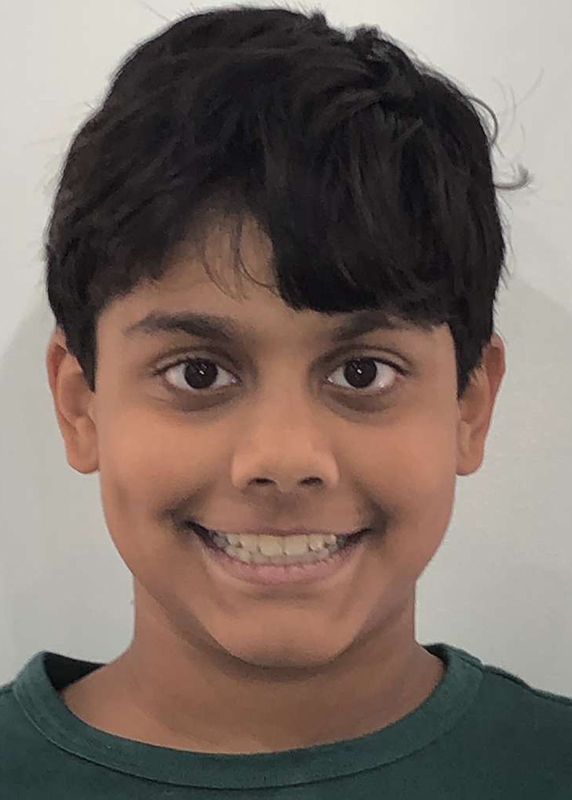

Actual Patient: Arjun

Before

After

Before

After

Severe crowding, narrow jaws, deep bite